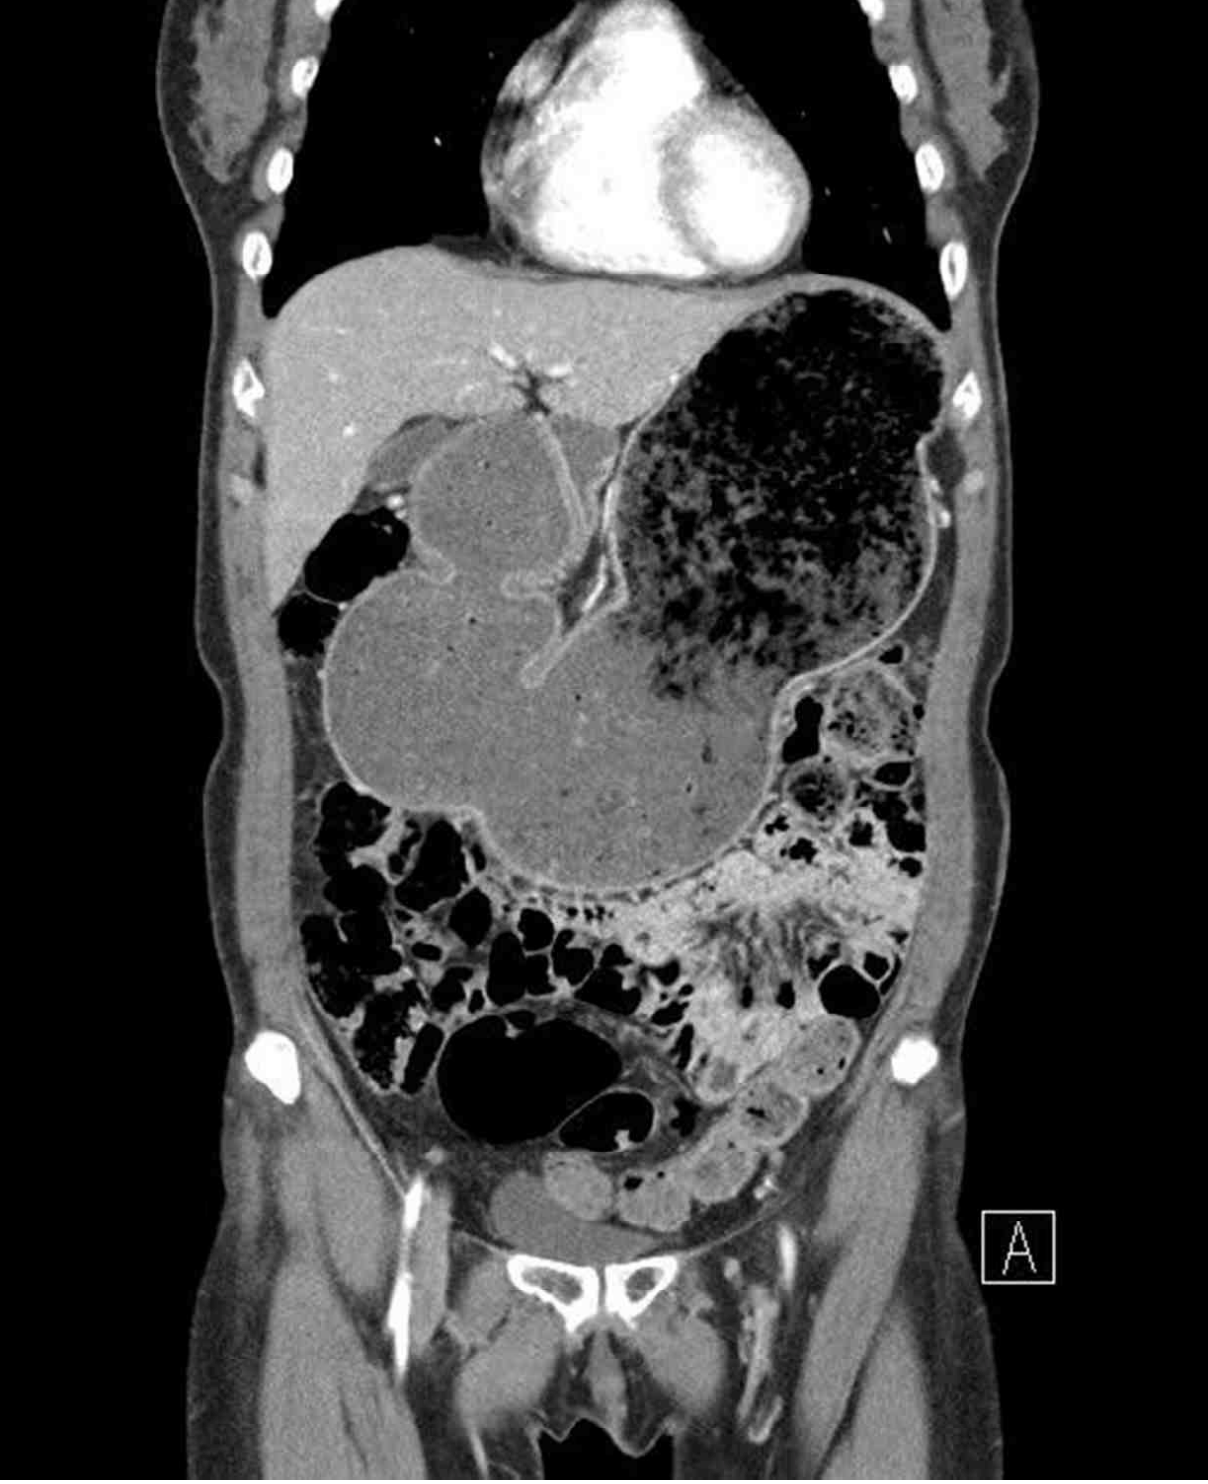

53세 여자가 1주 전부터 토해서 병원에 왔다. 3개월 전부터 소화가 잘되지 않고 속이 더부룩하였으며, 밥을 먹으면 증상이 더 심해져서 죽이나 미음을 먹었다고 한다. 2년 전 위궤양으로 진단받고 약물 복용하다가 자의로 중단하였다. 혈압 120/80 mmHg, 맥박 70회/분, 호흡 18회/분, 체온 36.7℃이다. 윗배가 불러있고 압통과 반동압통은 없다. 위내시경 사진과 복부 컴퓨터단층촬영 사진이다. 검사 결과는 다음과 같다. 치료는?

CT: Pyloric stenosis with proximal gastric distension

EGD: Chronic gastritis, pyloric stricture

• 신체진찰에서 상복부의 팽만이 관찰되며 복부 CT에서 유문부 협착과 이로 인한 proximal distension이 확인된다. EGD에서도 동일한 협착 소견을 확인하였으므로, 위궤양의 합병증으로 협착이 발생하여 증상이 발생한 것으로 판단된다.